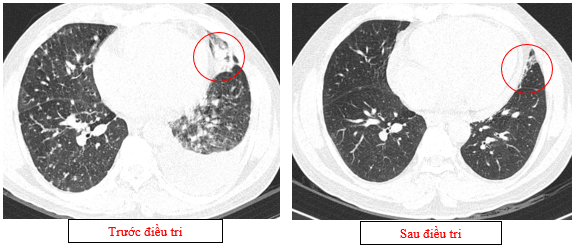

-         Chụp cắt lớp vi tính lồng ngực (11/2025): Màng phổi vùng rốn phổi trái dày,dày tổ chức kẽ vùng ngoại vi đáy phổi hai bên. Màng phổi trái có vài nốt đặc ngấm thuốc nốt lớn nhất kích thước 17x15mm. Khoang màng phổi hai bên không có dịch – khí (Tổn thương giảm đáng kể so với phim chụp 08/2025). Trung thất, rốn phổi hai bên, hố thượng đòn trái có vài hạch, hạch lớn nhất kích thước 12x6mm. Vài nốt đặc xương rải rác thân đốt sống, các cung xương sườn hai bên.

Hình 07: Hạch thượng đòn trái giảm đáng kể kích thước, từ 22mm còn 7mm sau điều trị.

Hình 08: Khối u đáp ứng gần hoàn toàn, chỉ còn tổn thương dạng kính mờ, các tổn thương dày tổ chức kẽ vách liên tiểu thuỳ, nốt đặc rải rác 2 trường phổi cũng gần như biến mất.

+      Khối u rốn phổi trái thoái triển gần hoàn toàn, các tổn thương dày tổ chức kẽ vách liên thùy và nốt đặc rải rác hai trường phổi phổi giảm rõ

+      Không còn tràn dịch màng phổi.

+    Hạch trung thất và thượng đòn: giảm kích thước rõ rệt, nhiều hạch không còn quan sát được trên phim chụp.